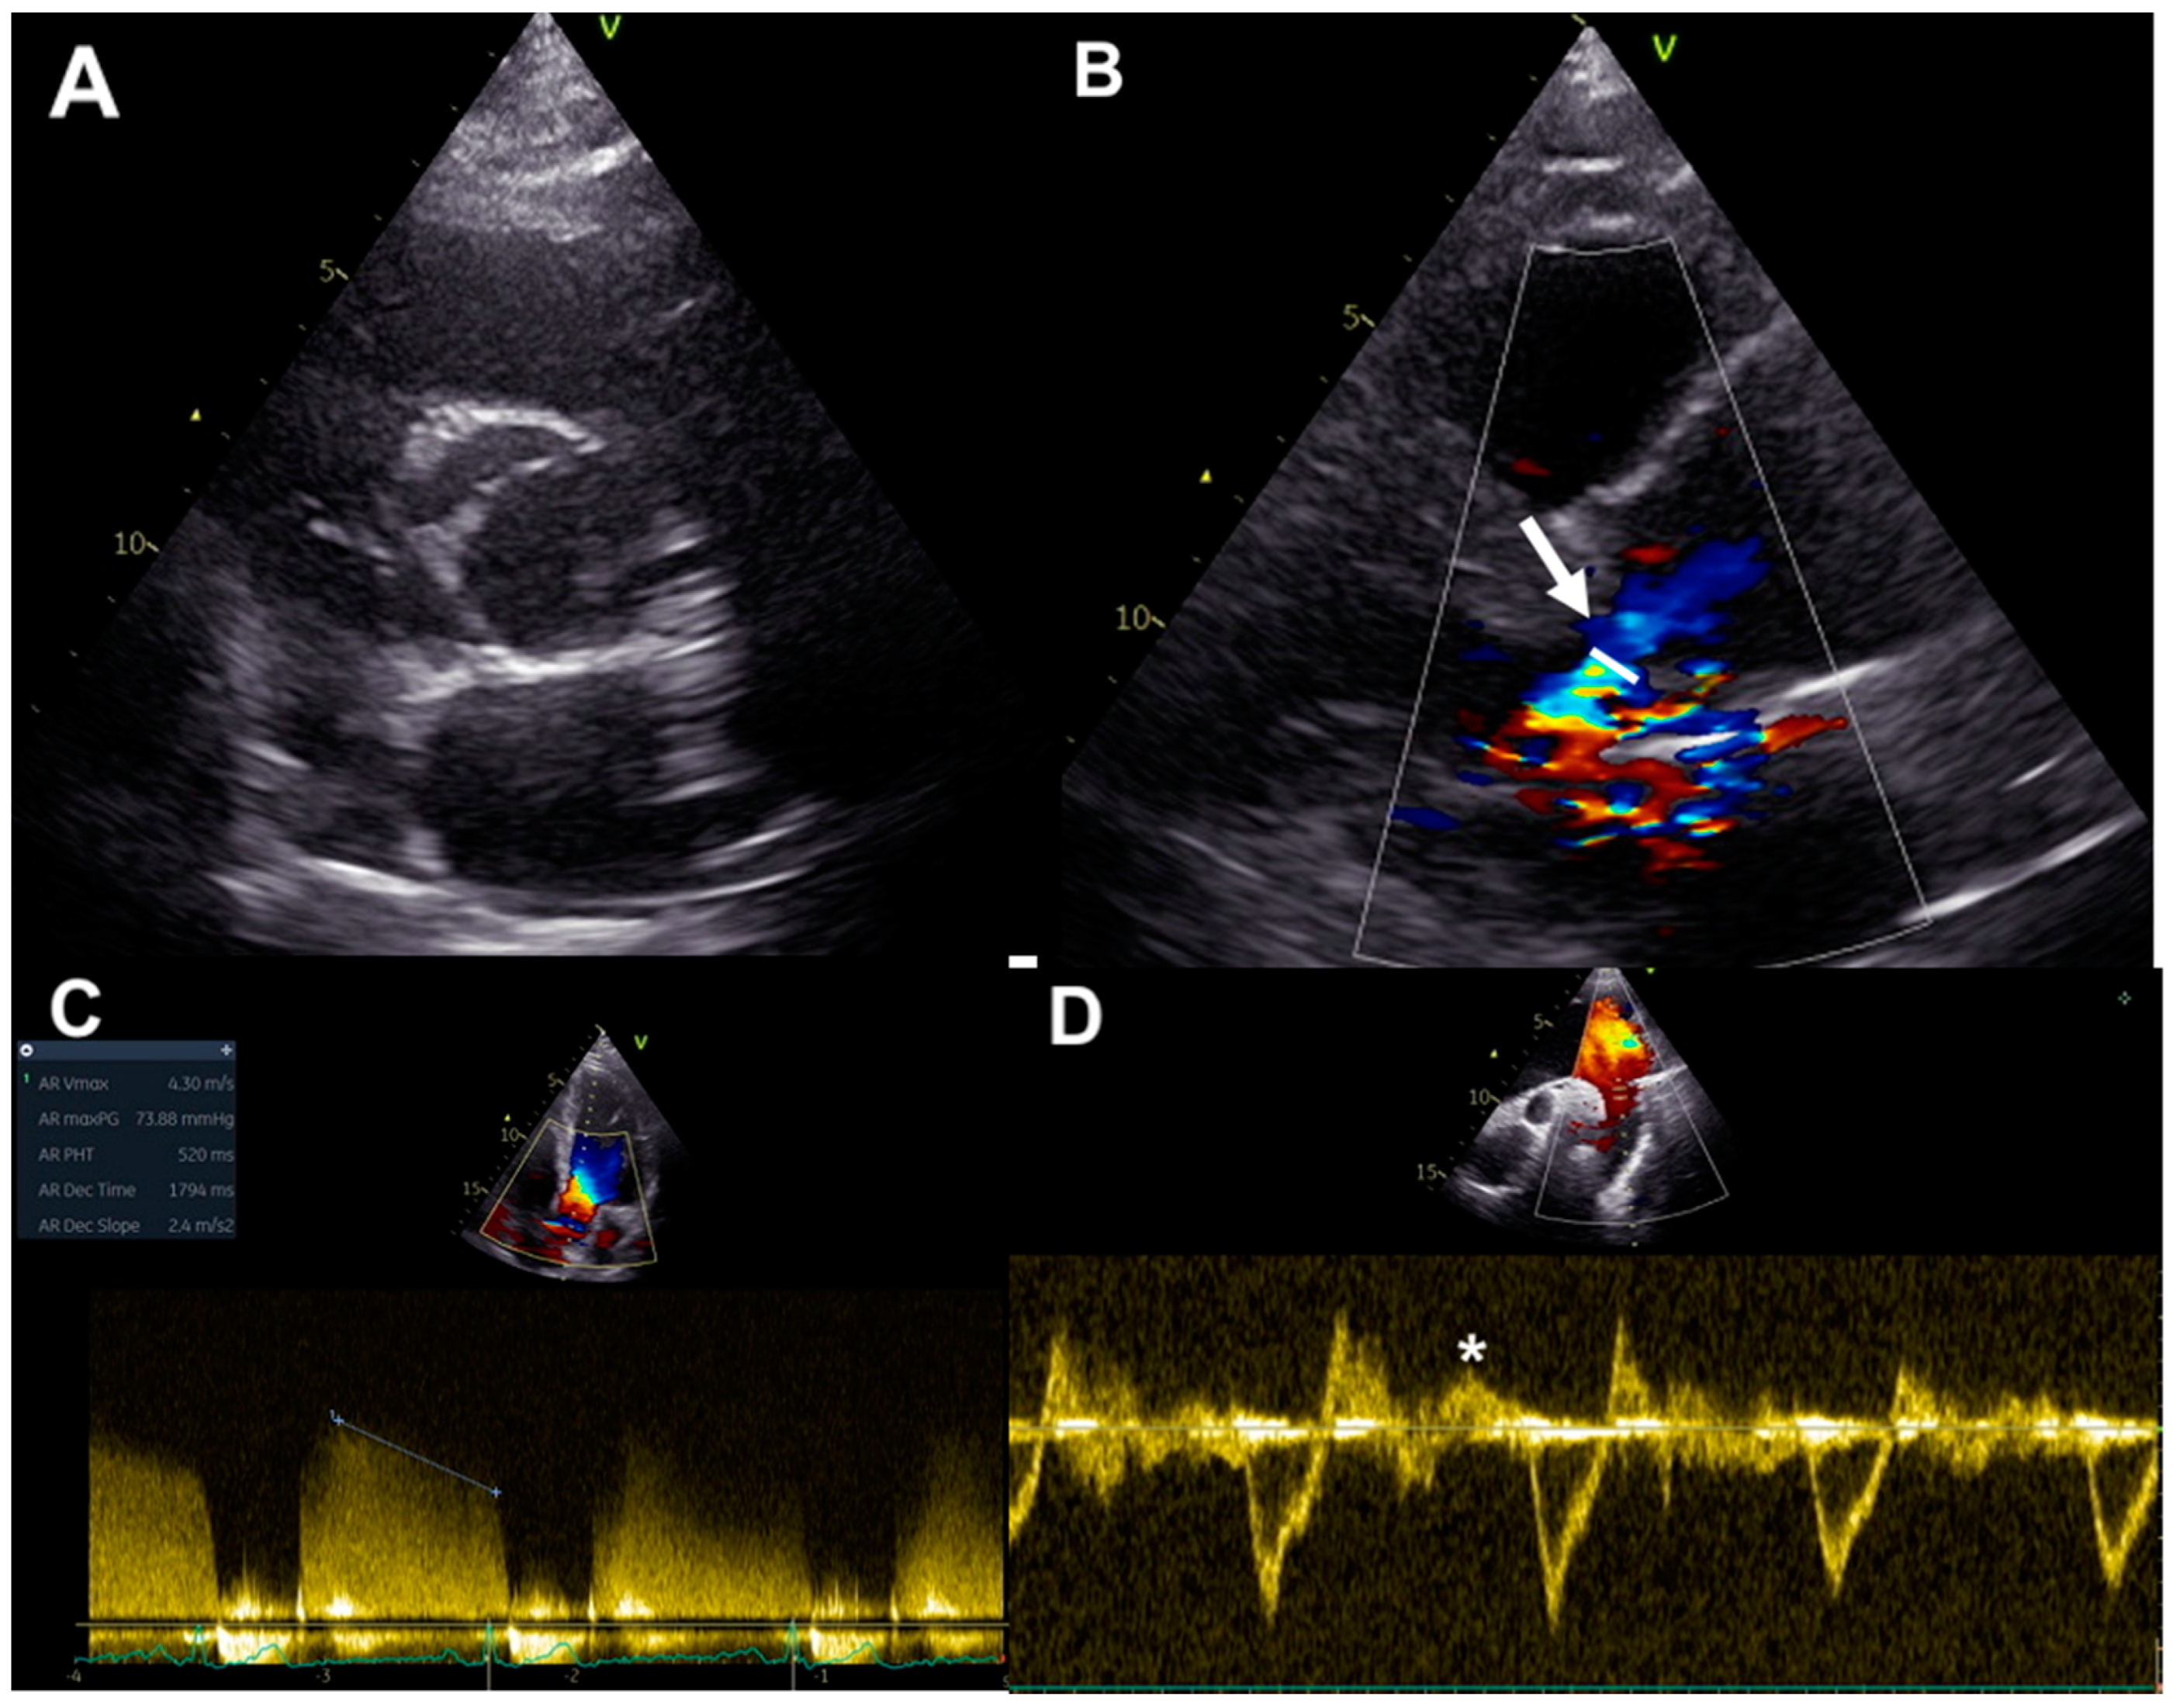

2.1. Qualitative and Quantitative Assessment